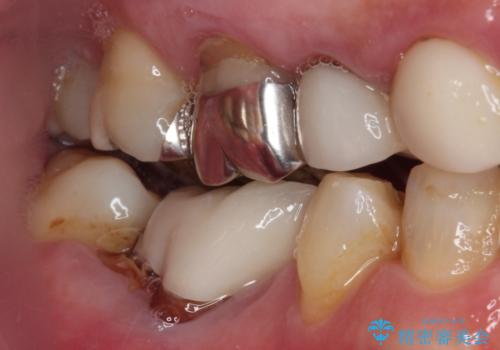

病変が大きかったことや、神経や血管が多く通る管が近いこともあり、抜歯即時埋入ではなく、骨の治癒が待ってから埋入を行う、従来の方法にてインプラント治療を行いました。